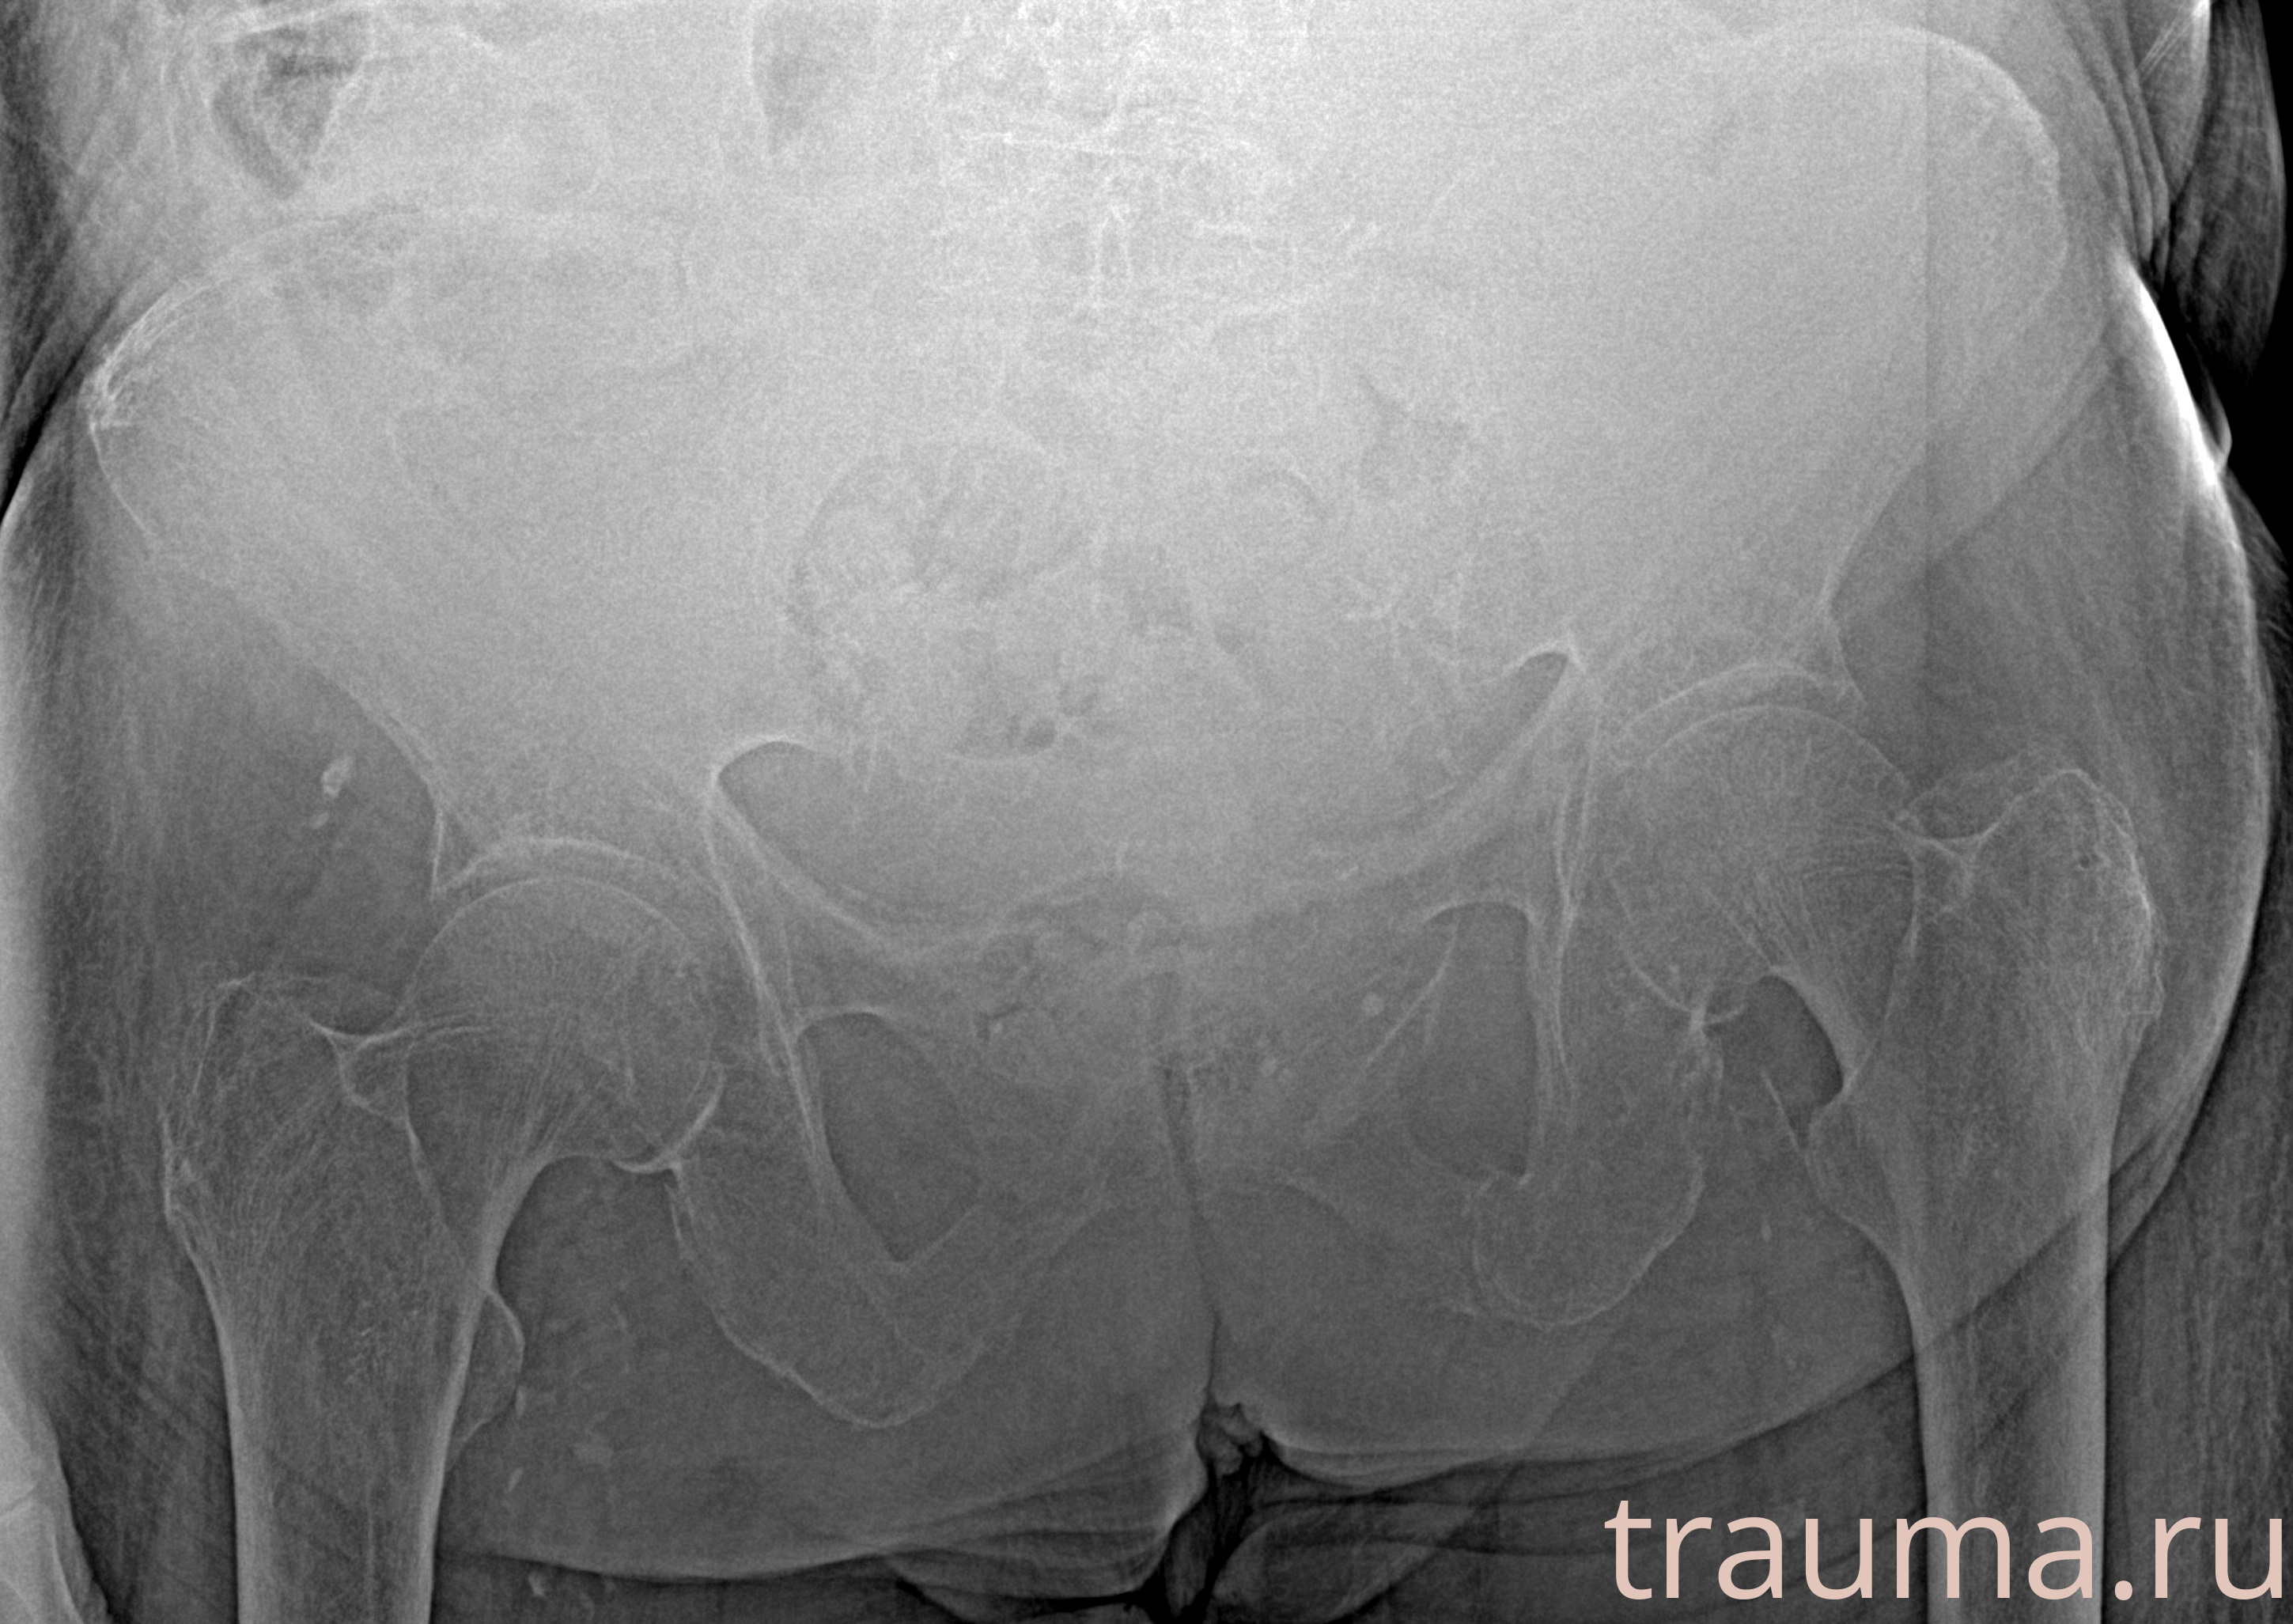

Рентгенограммы

Рентген на дому: по вашему адресу приезжает врач-рентгенолог, травматолог-ортопед с мобильным рентгеновским аппаратом, проводит диагностику травмы или заболевания, делает необходимые рентгенограммы, дает рекомендации по дальнейшему лечению. Получить качественные снимки в домашних условиях возможно благодаря уникальной методике, разработанной МосРентген Центром для института  Склифосовского